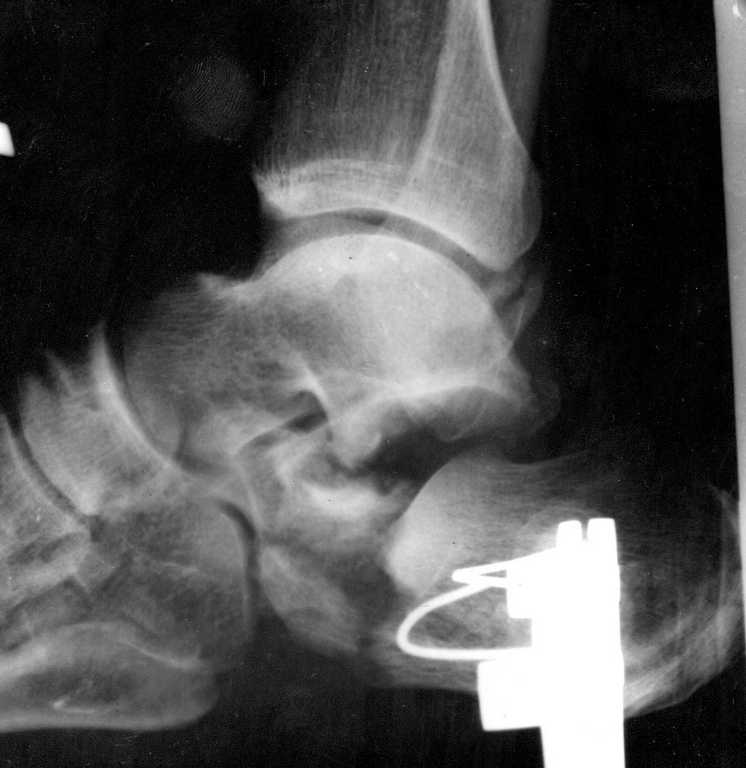

Больной поступил в травматологическое отделение 21.07.09, упал с высоты 3 метров. При

поступлении скелетное вытяжение. 24.07.08 рентгенологический контроль. Подскажите

какой метод лечения приемлем для данно ситуации?